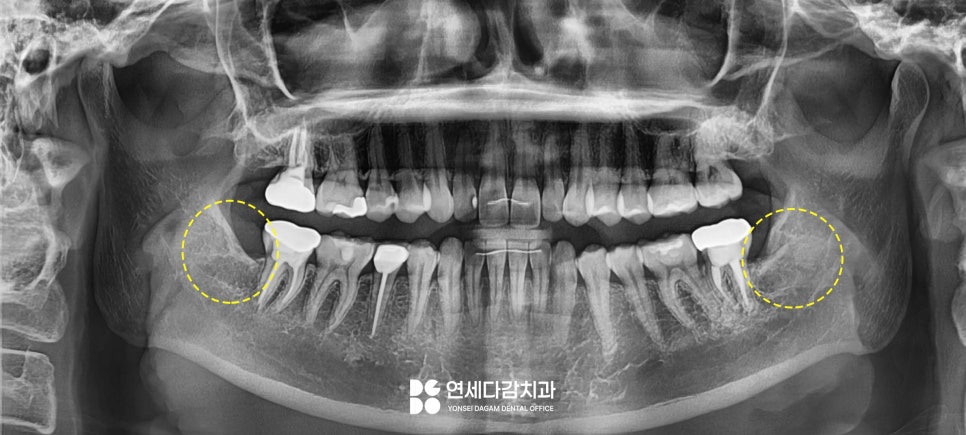

우선 일반 파노라마를

촬영하여 교근을 잘 살펴봅니다.

이때 턱 근육이 비대해져

양측 교근과 측두근이 과도하게

발달된 것을 알 수 있었습니다.

또한 부분 맹출 된 사랑니 부위에

음식물이 많이 끼면서

잇몸이 심하게 붓기도 합니다.

붓기가 심하면 입이 잘 다물어지지

않는 경우도 있으니

이런 경우엔 사랑니도 같이 치료하는 것이 좋습니다.

턱관절 치료와 함께

평소 불편했던 사랑니도 발치하여

삶의 질을 개선할 수 있었습니다.